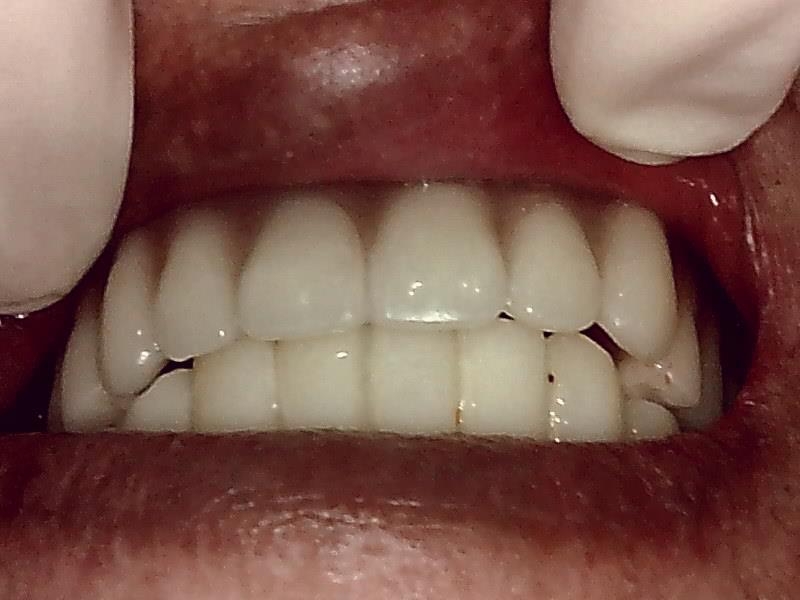

上部構造装着した状態です。

下顎のインプラント装着した、上顎総義歯との被蓋関係

完成後、予後経過はとても良好な状態です。